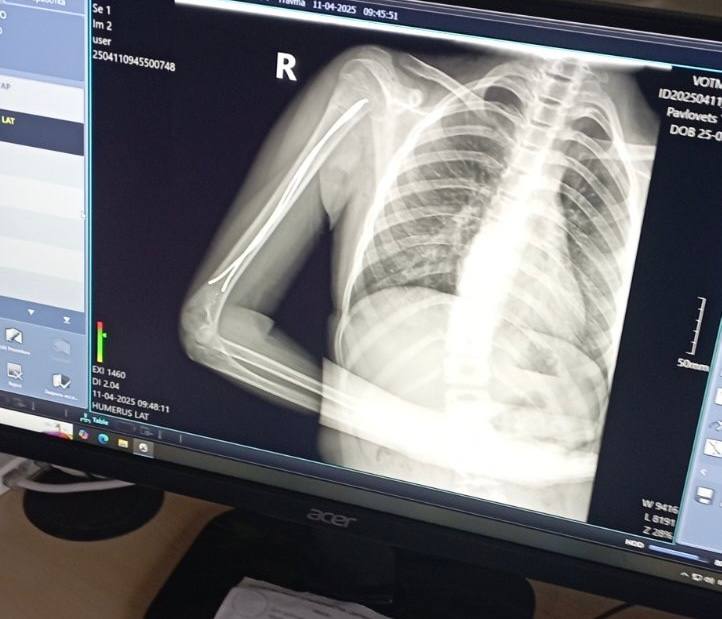

Ще одна пацієнтка відділення — 11-річна футболістка Юля, яка невдало впала на плече під час гри. Як наслідок — перелом плечової кістки зі зміщенням.

Раніше через такий перелом довелося б носити велику гіпсову пов’язку на руці — від кисті до плеча, також гіпс накладали б для фіксації і на обидва плеча. Після операції через 2-3 дні дівчинка вже вільно рухає рукою, не відчуває обмежень. На руці залишиться лише невеликий шрам 2-3 сантиметра. Через декілька тижнів дівчинка зможе повернутися до занять футболом.